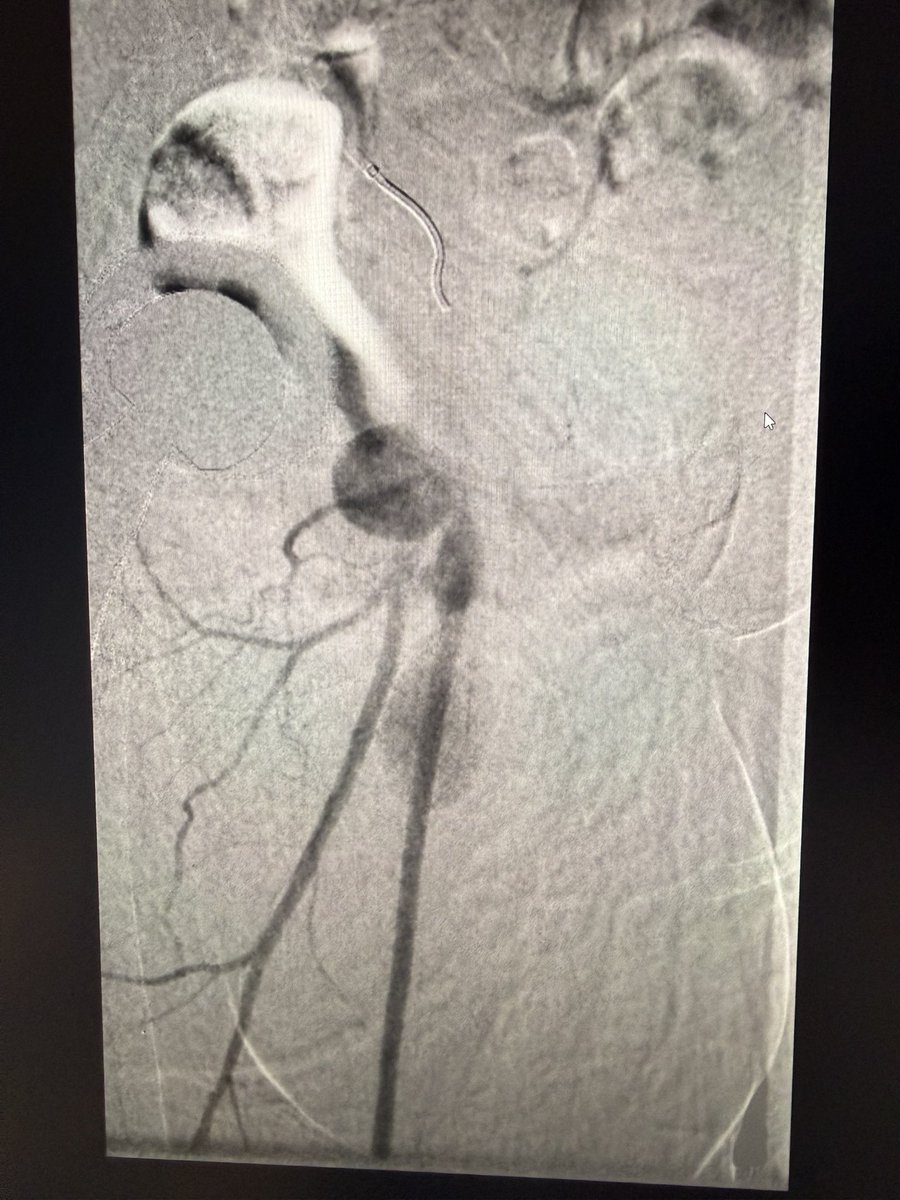

17 yrs old male, keen football player.sudden onset pain in right leg and foot. Absent foot pulses and pale foot. CTA below. What is the diagnosis?

Look at cross sectional image?!

How would you treat?